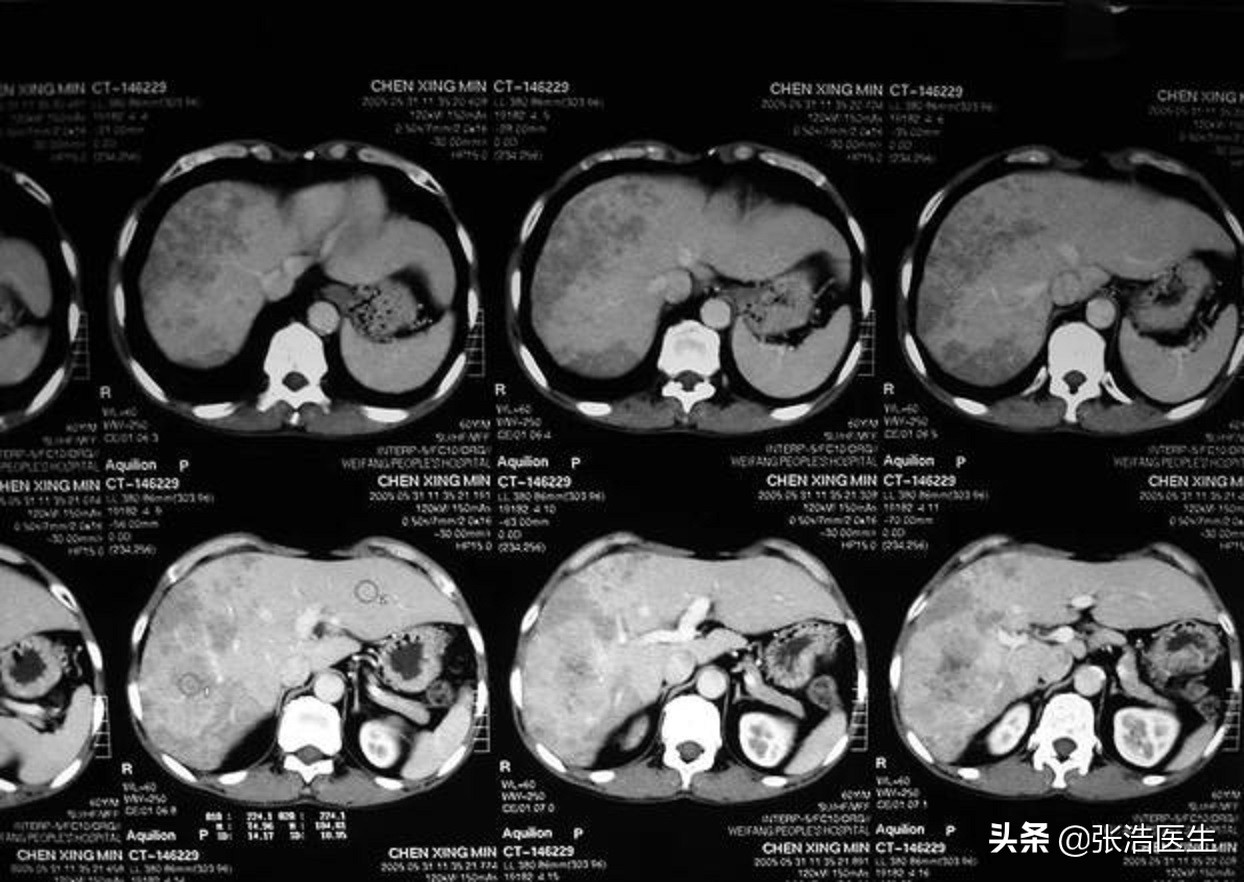

如胰腺癌、肝癌等会导致胆管堵塞,进而形成黄疸,胆汁排泄不畅,导致胆汁内的胆汁酸盐刺激皮肤末梢,就会出现瘙痒,另外一些容易转移到肝、胰腺等的癌症在发生转移后也会出现胆汁升高而导致的皮肤瘙痒;如肺癌会导致异位激素分泌异常,也可能出现皮肤瘙痒的这种。